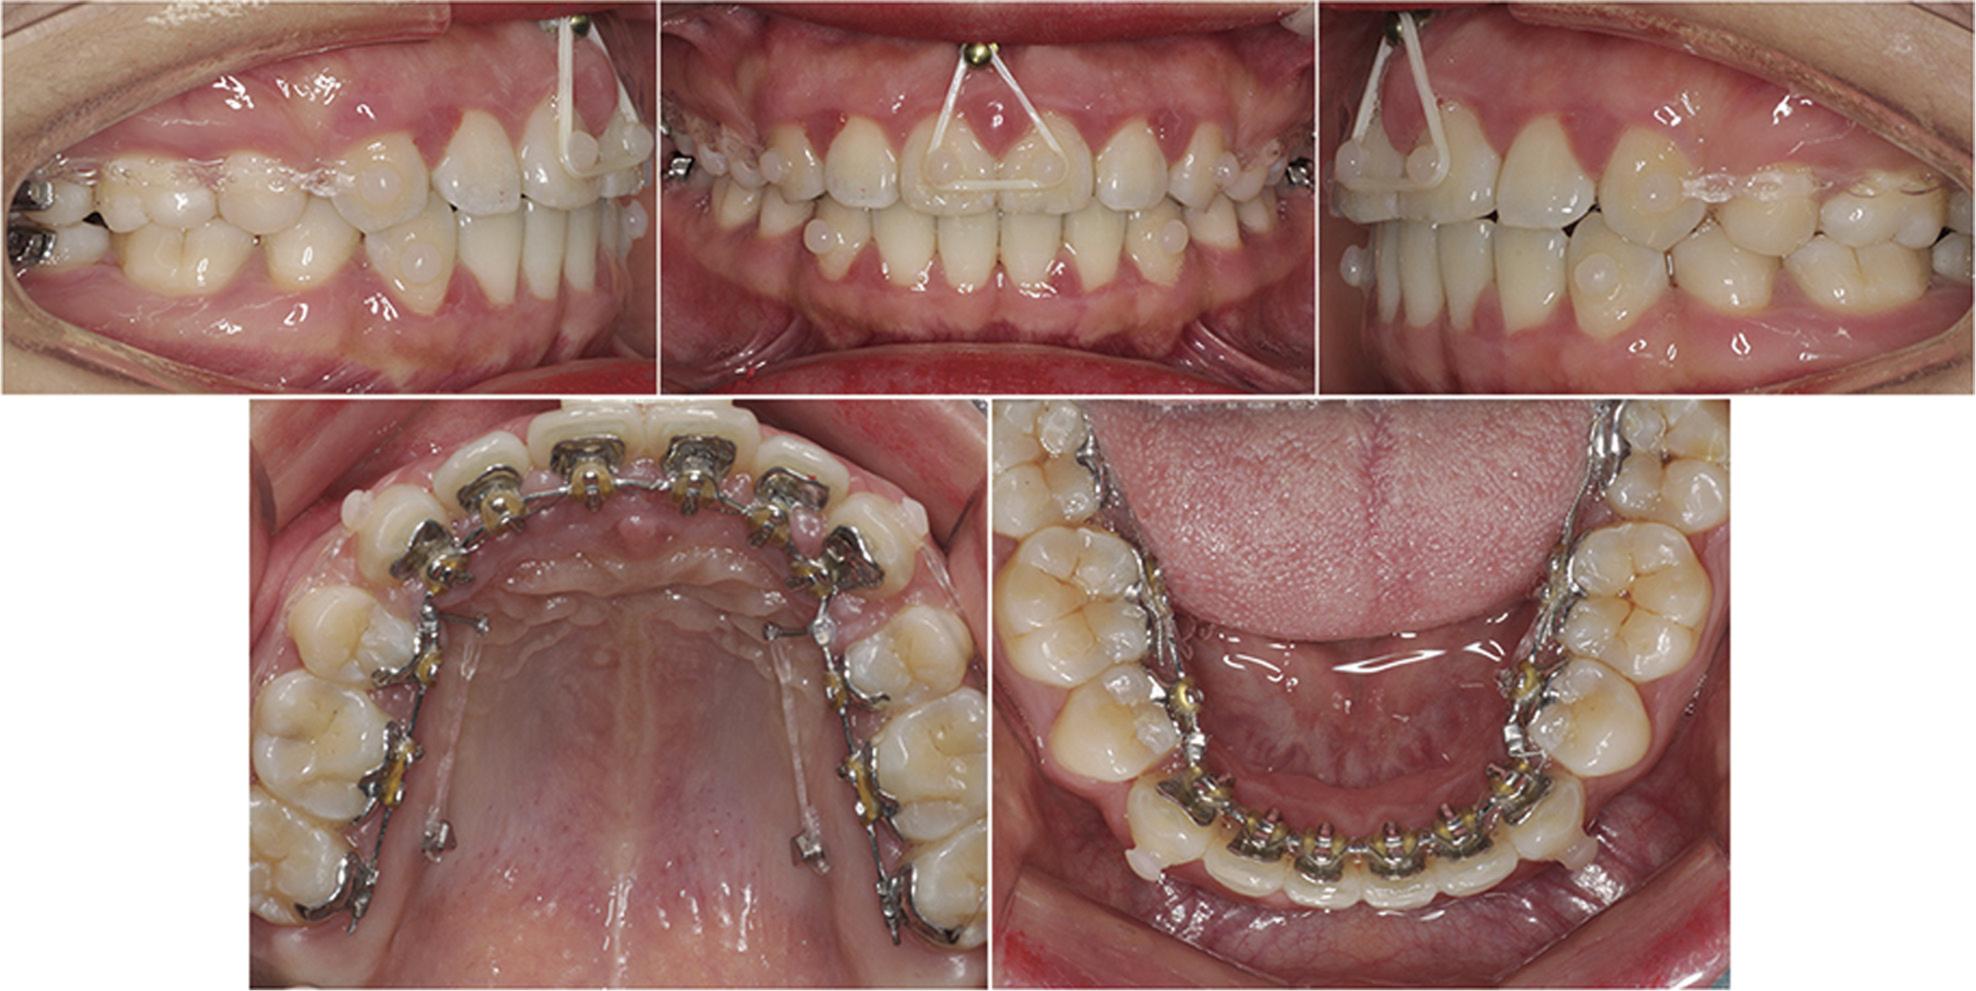

Figure 7.

A micro-screw was inserted between maxillary central incisors in the mucogingival junction and assisted in intruding the anterior teeth.

In the last three months of this phase, a micro-screw (diameter, 1.5 mm and length, 8.0 mm; SYNTEC Scientific, Taiwan, CN) was inserted between the maxillary central incisors at the mucogingival junction. Once the micro-screw was placed, a 100 g of intrusive force was applied by a latex elastic of 3/16-inch (3.5oz, 3M Unitek, St Paul, Minn, USA) from the micro-screw to the maxillary incisors (Figure 7). The treatment time for step 2 was short and lasted about 7 months.

Step 2: en-masse retraction of the maxillary and mandibular anterior teeth and intrusion of the maxillary anterior teeth (7 months).

Two micro-screws (Damon Q Screw: diameter, 1.4 mm and length, 8.0 mm; Ormco, Calif., USA) were bilaterally placed in the maxillary palatal alveolar bone between the first and second molars at a position 8 mm gingival to the arch wire. Long lever-arms (7.5 mm), whose height was set to the level of the plane created by the micro-screws and the centre of resistance (CRes), were fixed to a 0.025˝ × 0.017˝ stainless steel ribbon-wise wire at the distal of the cuspid teeth. Lingual lever-arms and micro-screws provided the desired force to the CRes to control anterior torque during the en-masse retraction.5,7

Elastic latex chains which applied 150 g of retraction force (3M Unitek, St Paul, Minn, USA) were attached from the micro-screws to the lever arms for en-masse retraction of the maxillary anterior teeth using sliding mechanics. Stainless steel ligature wires (0.20 mm) were used to continuously ligate the anterior teeth as a unit. The six mandibular anterior teeth were similarly retracted by applying 150 g of retraction force and employing sliding mechanics. ‘Double cable’ mechanics were used to prevent a transverse bowing effect.